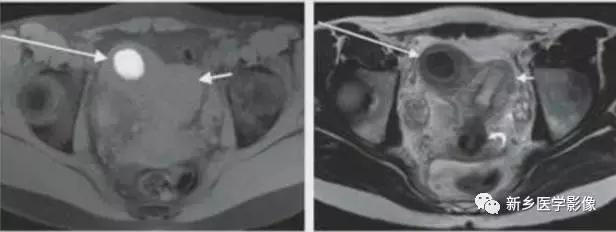

上图:单角子宫(II-B残角,有内膜腔,不相通):右侧残角宫腔内积血,为短T1长T2异常信号。左侧单角子宫,见带状结构,呈香蕉样。